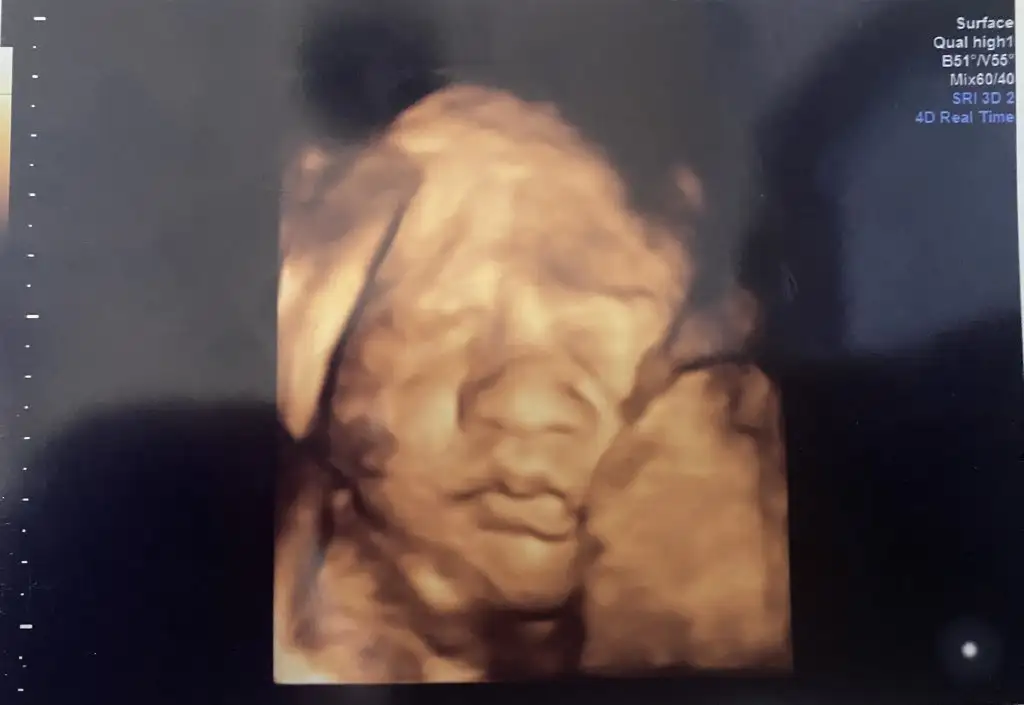

Bebeğimin cinsiyeti